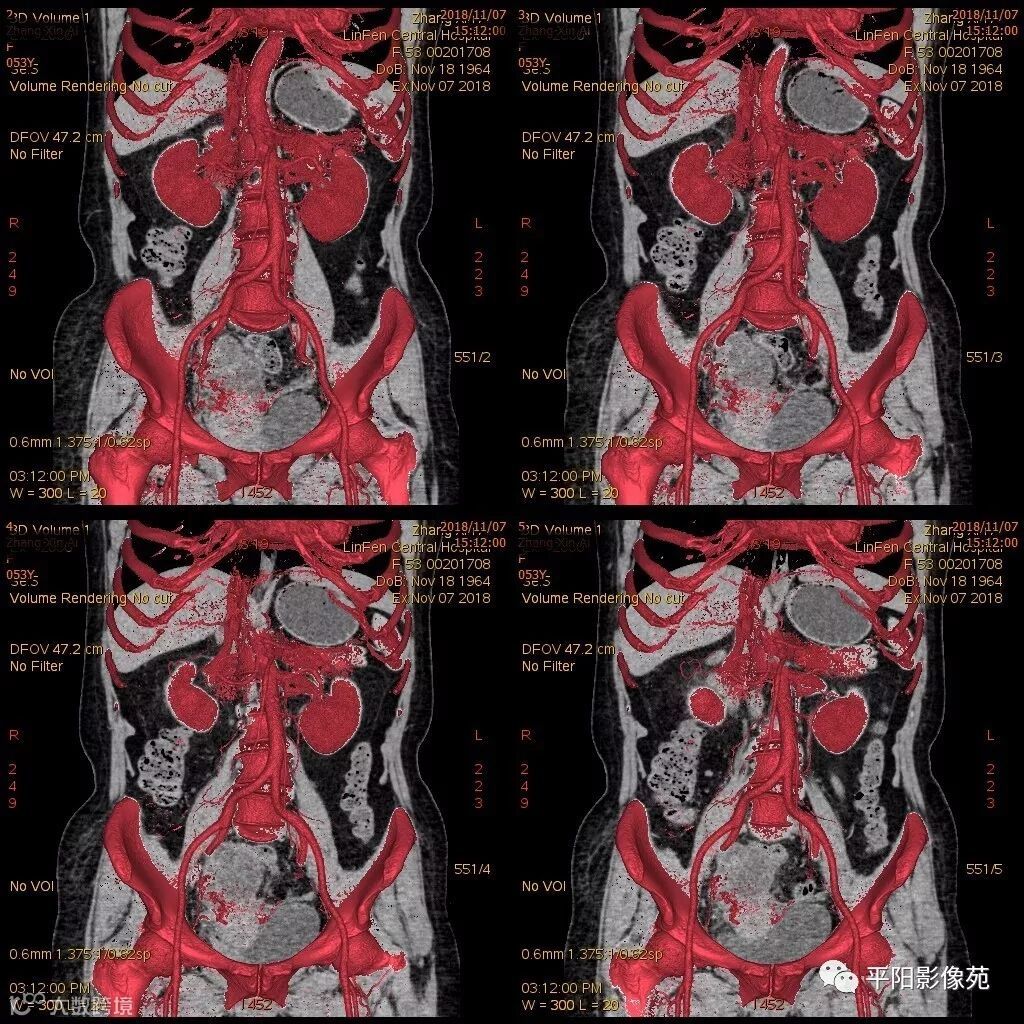

影像特点

右附件区薄壁囊性病变,壁明显强化,边界不清,供血动脉源自子宫动脉,且局部动脉血管增多;其内侧可见卵圆形无强化囊性病灶。

附件区病变多见于卵巢,以囊性为主的病灶多为卵巢囊肿、粘液/浆液性囊腺瘤、皮样囊肿等,这些病灶都具有鲜明瘤体结构,且壁强化多为轻-中度,供血动脉多源自卵巢动脉;而本例患者右附件区薄壁囊性病灶,多位置观察形态为迂曲管状,且壁有明显延迟强化,供血动脉源自子宫动脉,较对侧血管丰富,故而考虑源自输卵管或子宫病变,但子宫发生的薄壁囊性病变较少,多见于子宫肌瘤囊变,完全囊变者少见,且形态轮廓与肌瘤相同为球形故而排除,结合患者腹痛前有感冒病史,且有压痛,因此考虑输卵管积脓可能。其内侧无强化囊性肿块,考虑卵巢囊肿可能。

主要与卵巢囊肿伴感染、皮样囊肿、卵巢囊腺瘤等鉴别,当病变表现相似时,可根据供血动脉以兹鉴别,卵巢病灶为卵巢动脉供血,其自腹主动脉,输卵管病变多由输卵管动脉供血,源自髂内动脉→子宫动脉→输卵管动脉。